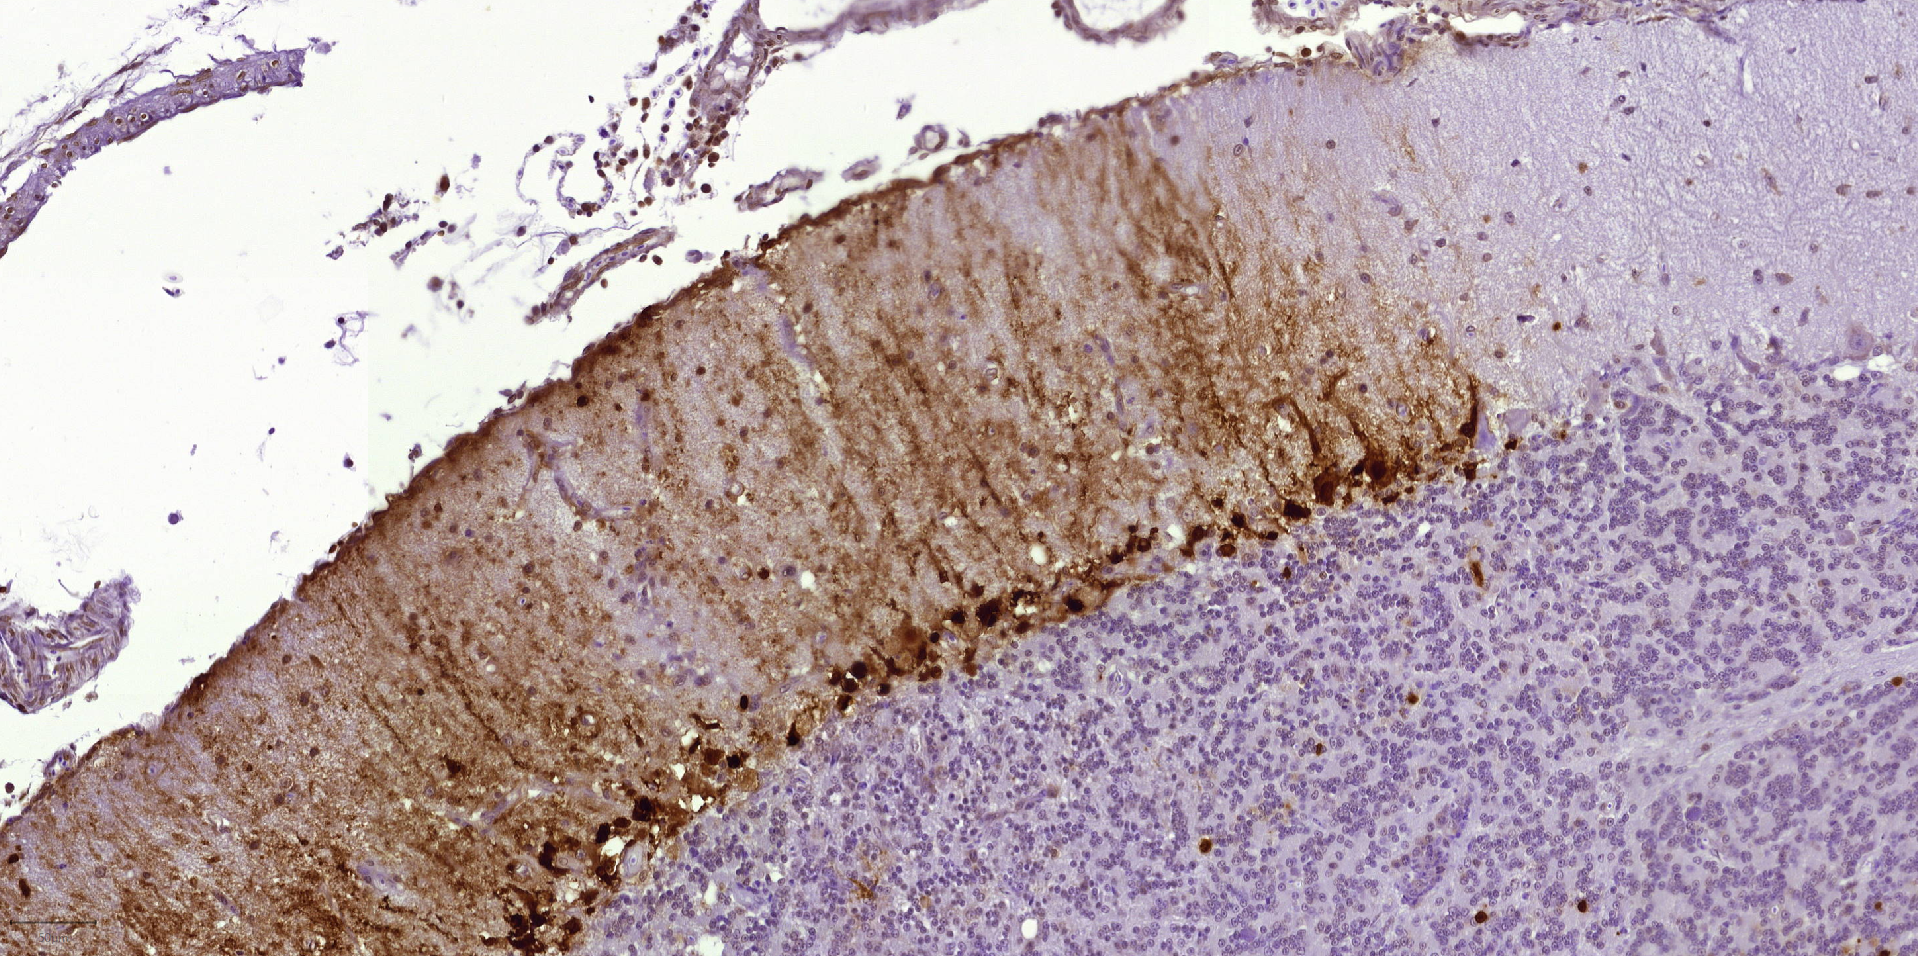

Images de cerveau de poulet et de canard observé au microscope, avec le virus marqué en marron.